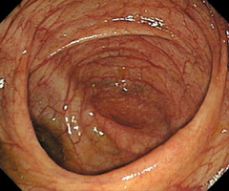

장청소의 중요성

일곱 번째 방법으로는 장청소를 들 수 있습니다. 장청소 방법에는 여러 가지가 있지만, 천연 성분으로 이루어진 클렌즈 음료나 스무디를 활용하는 것이 가장 좋습니다. 레몬, 오렌지, 참외 등의 과일과 함께 다양한 채소를 활용하여 블렌더로 갈아 드시는 것도 효과적입니다.

장청소는 정기적으로 진행하는 것이 이상적입니다. 과도한 숙변 제거는 오히려 장의 건강에 악영향을 미칠 수 있으니, 주의가 필요합니다.